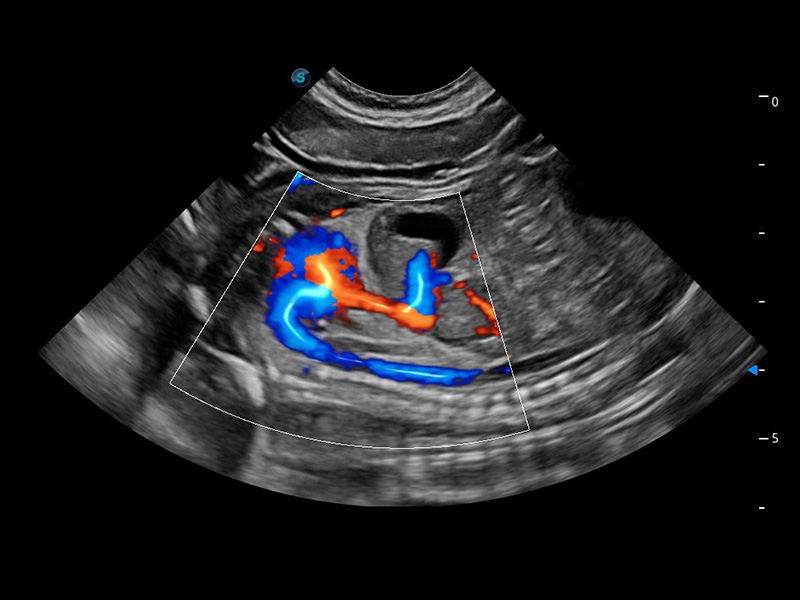

ProPet 60 作为一款高端台式动物超声设备,为动物医生的日常诊断提供了一系列贴合动物临床需求、解决临床实际问题的高级成像功能。凭借全系列高清探头,满足医生对腹部、心脏、生殖、浅表、肌骨等成像的所有需求,切实帮助您提升检查效率,提高诊断信心。

兽用彩色多普勒超声诊断系统

动物是人类最亲密的朋友和最值得信赖的伙伴。亚星官网也一直致力于探索动物专用的超声影像解决方案。 全新推出的ProPet系列,是亚星官网在动物超声影像智能化、专业化、精准化的一次跨越式革新。动物不能用言语来表述自己的不适,通过超声影像,ProPet系列搭建了动物医生与不同物种沟通的“桥梁”,为动物医生注入了“治愈之力”。